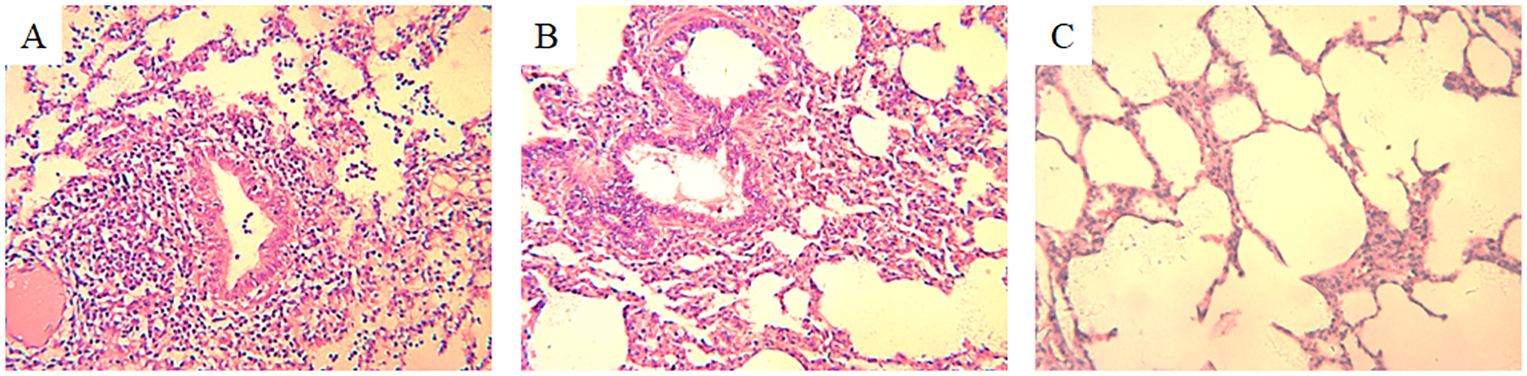

Histopathological examination of H3N2 SIV-positive pig lung tissue showed significant lung lesions. Extensive peribronchial and perivascular infiltrates of monocytes were observed, indicating a strong inflammatory response. In addition, thickening of the alveolar septum and partial filling of the alveolar space by exudate suggest interstitial pneumonia (Figure 1A). Bronchial epithelial damage is evident, as well as an infiltration of inflammatory cells in the bronchioles and surrounding area (Figure 1B). In contrast, the lung tissue of an uninfected control pig exhibited normal histological features, including intact alveolar structures, thin alveolar septa, and a lack of inflammatory cell infiltration (Figure 1C). These findings highlight the pathogenic effects of H3N2 SIV on the respiratory system, leading to severe pulmonary dysfunction and associated clinical symptoms in infected pigs.

Figure 1. Histopathological changes in the lung tissue of a pig infected with H3N2 SIV. (A) Inflammatory cell infiltration, including neutrophils and lymphocytes, can be seen around the bronchioles, with cellular debris partially obstructing the bronchiolar lumen (HE×200). (B) Interstitial inflammation and alveolar septal thickening with significant inflammatory cell infiltration and edema in the interstitial spaces of the alveolar region (HE×200). (C) Normal lung tissue from an uninfected control pig, showing clear alveolar spaces and intact alveolar septa without signs of inflammation or cellular infiltration (HE×200).